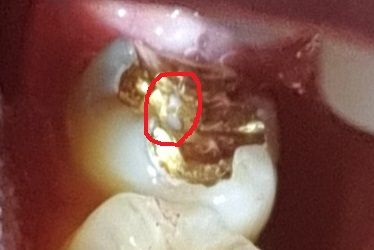

어금니 골드 인레이가 1년 안되고 떨어져서 재부착했는데 좀 불편 하다고하니 저렇게 교정해주신다고 뚫어주셨는데 안에 치아가 보이네요

교합면이라 좀 불안하기도해서 다양한 전문의분들의 고견을 듣고 싶습니다

• 1번 째 사진